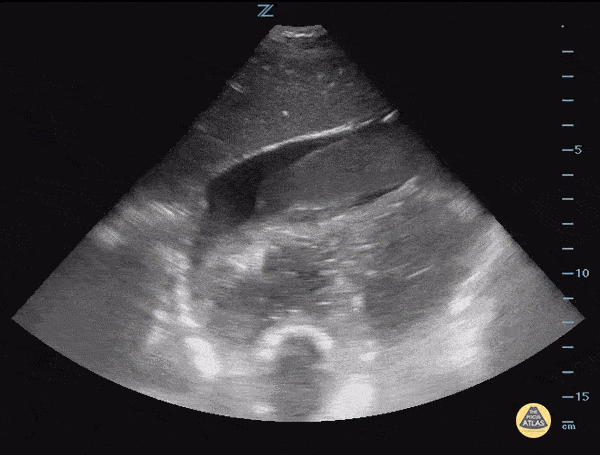

This is a subcostal view of a patient presenting after a motor vehicle collision. The image demonstrates a pericardial effusion containing a large hypoechoic mobile structure concerning for hematoma. Image courtesy of IUEM Ultrasound Original Twitter post can be found here.